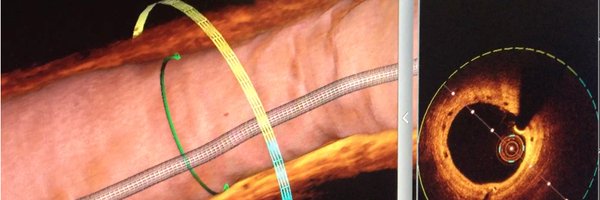

@VPanoulas

The unparalleled simplicity and beauty of ⁦@ShockwaveIVL⁩ #CardioTwitter #radialfirst #CardioEd